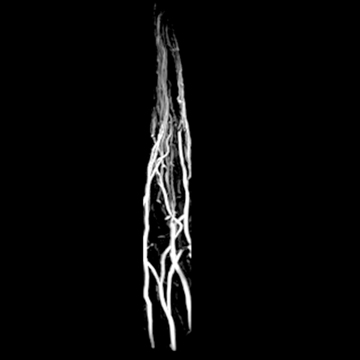

頭部MRA

matrix 320, FOV 220 mm- 頭部MRA